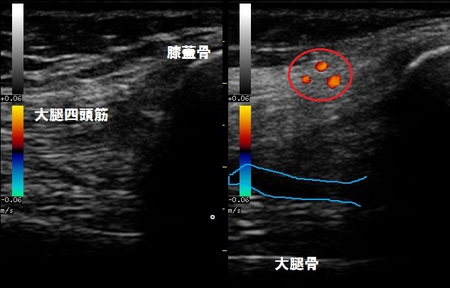

右膝関節上部 超音波長軸像 左膝関節 患側

超音波検査をしたところ、膝蓋骨に骨折はありませんでしたが関節内に関節液が過剰に溜まって(右画像の

青線)、大腿四頭筋は損傷し腫れている様子が認められました(右画像の赤丸)。